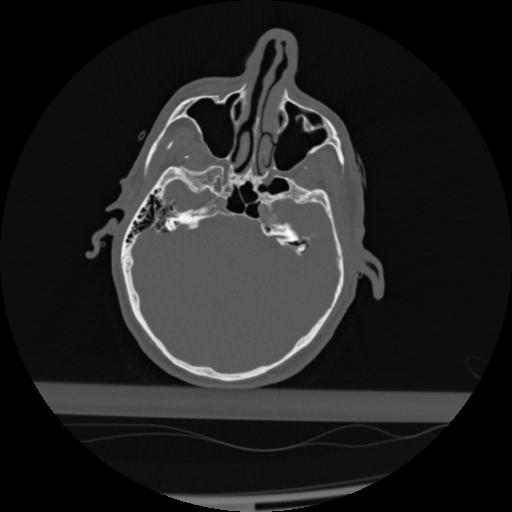

22 ANGIO,CE,Vol,0.5,ANGIO,,